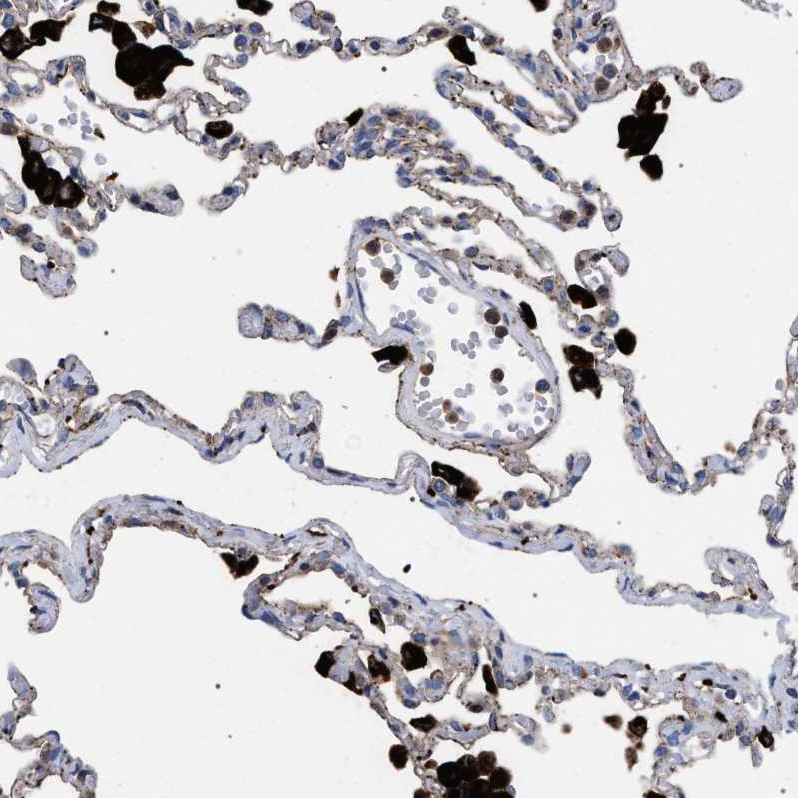

Immunohistochemical staining of human lung shows very strong granular positivity in cytoplasm in macrophages.